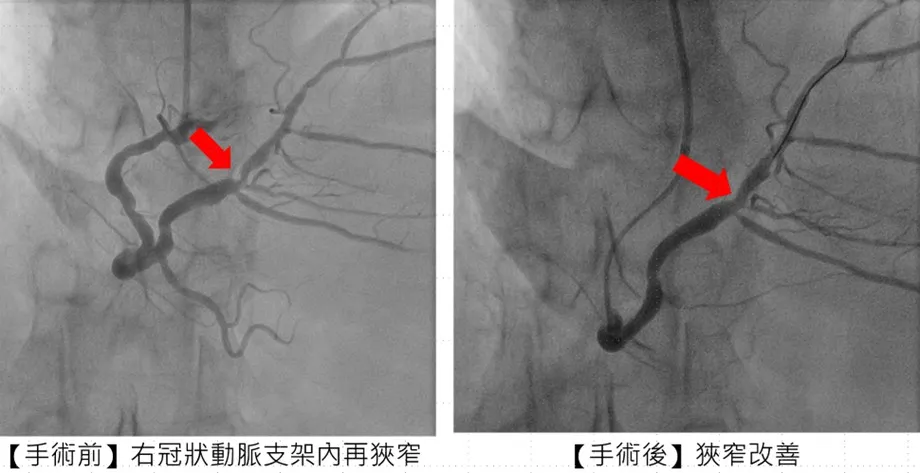

针对从花莲远道而来的张姓患者治疗过程,市医副院长兼心脏科专家陈建钧医师进一步说明,病人有多次支架再阻塞的病史,加上长途奔波与生活压力,病情更加复杂。经团队缜密评估后,决定采用「刀片气球」及「涂药气球」治疗,既能打通血管阻塞,也可降低再度狭窄的风险,大幅缩短康复时间。手术全程顺利,患者隔日即可出院,术后更能安心规划生活与健康管理。